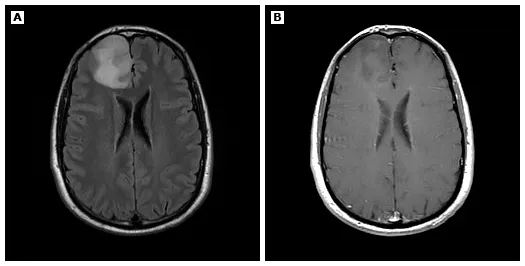

40岁男性,因首次全面性强直-阵挛发作就诊,行头颅MRI检查。术后病理证实为WHO 2级胶质瘤。(图A)轴位FLAIR序列示右侧额叶一T2高信号、膨胀性占位病变;(图B)增强后轴位T1加权像未见明显对比剂强化。